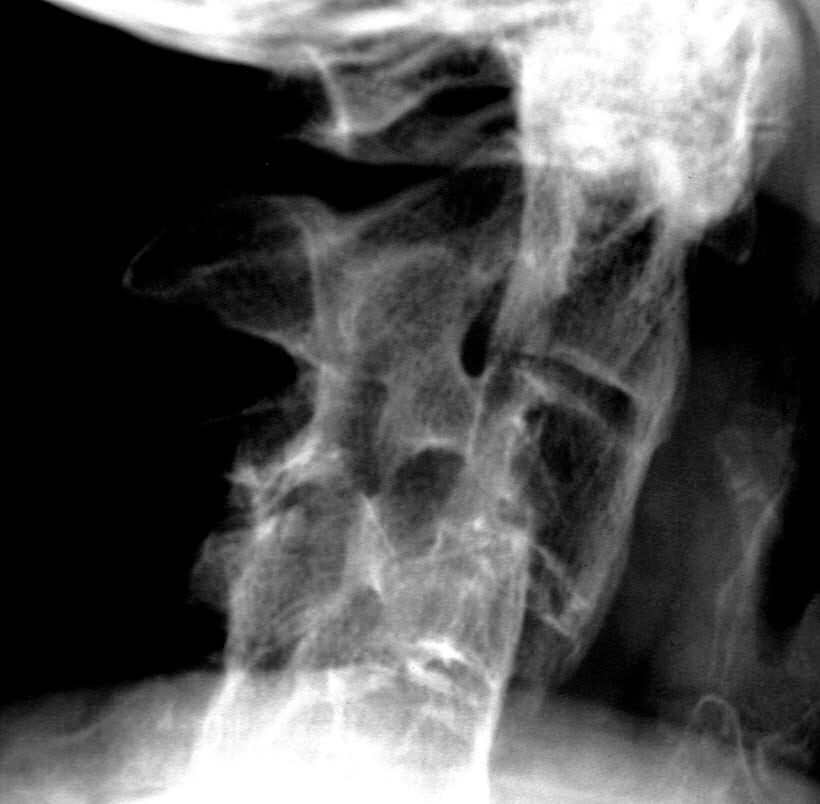

– Uram, ezek nem az ön felvételei… itt valami tévedés lesz…

– Ez egy gyerek gerince… a koponya és a csípőkép pedig…